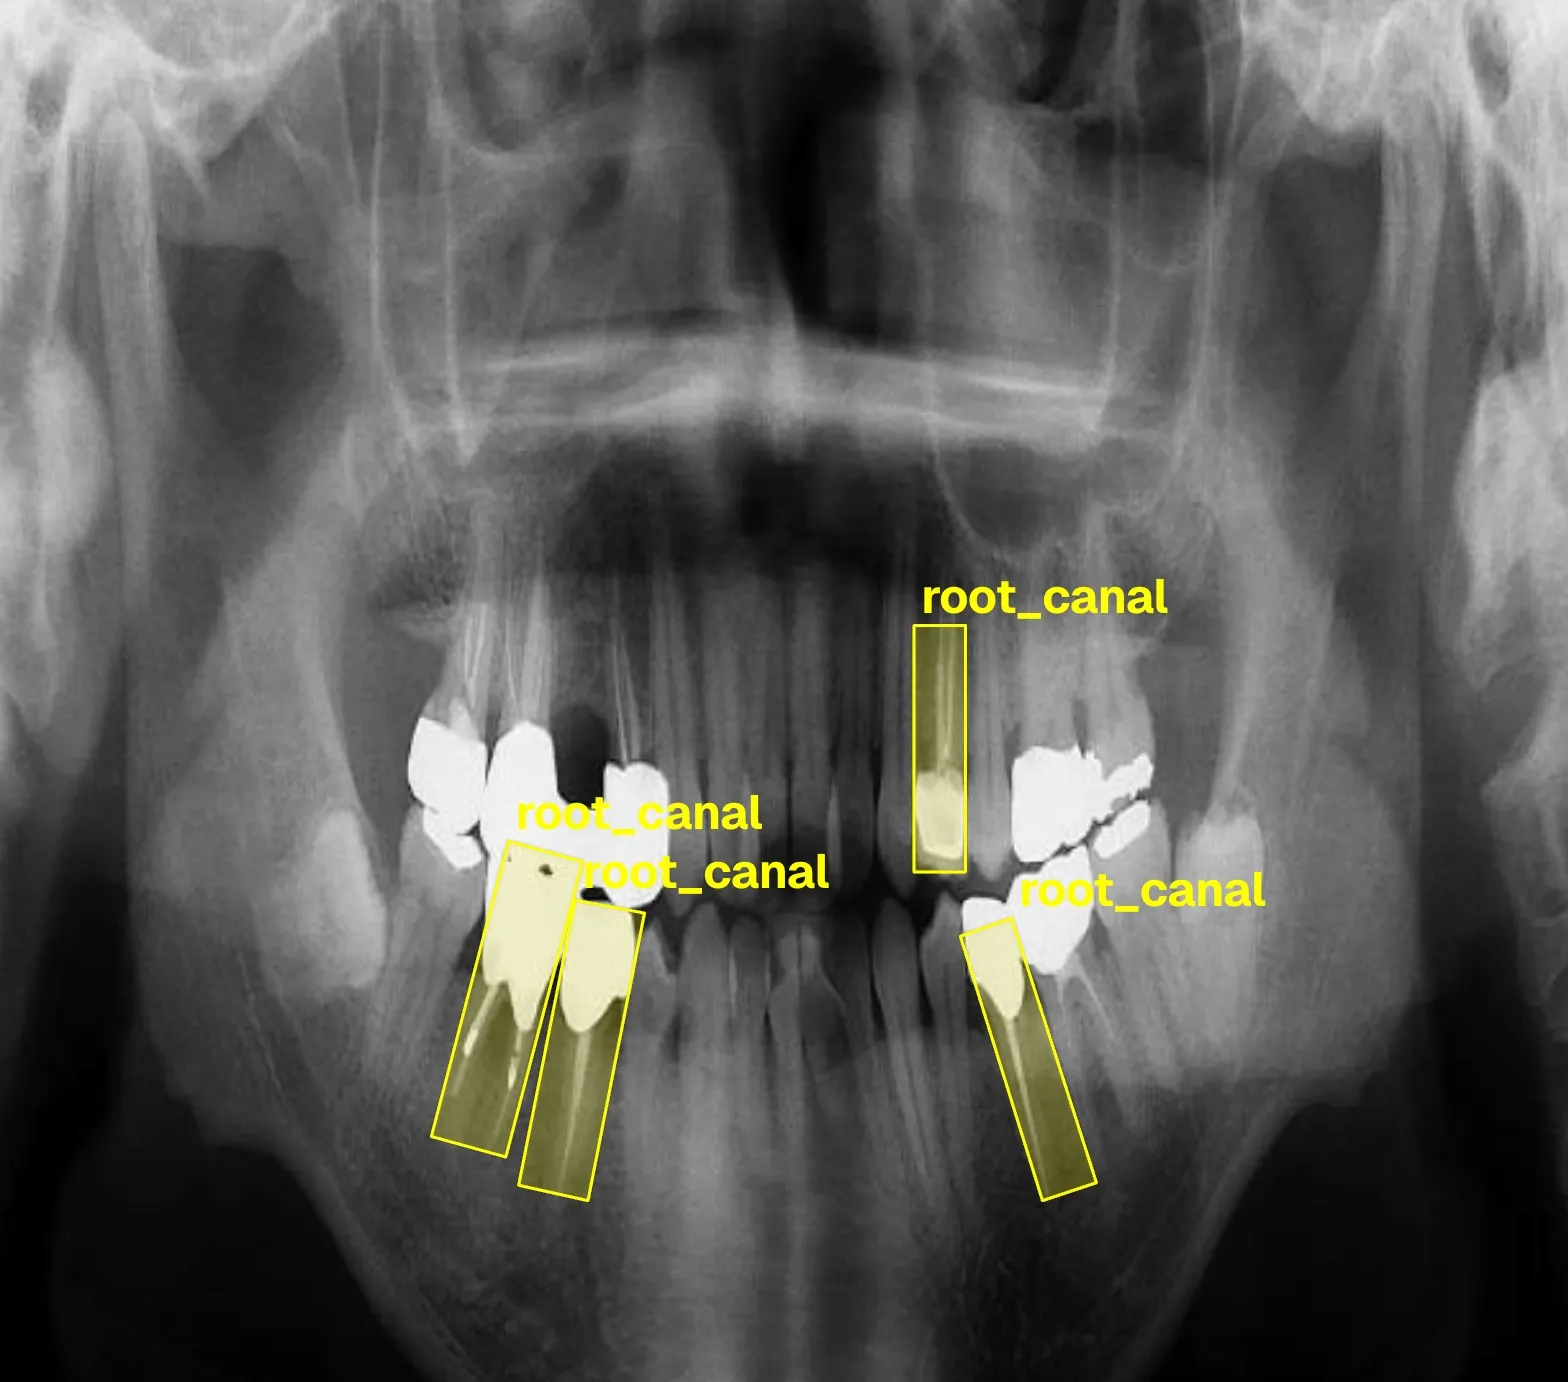

- Root canal therapy